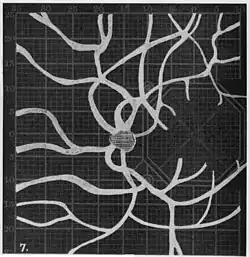

Angioscotomas were first discovered and mapped out by John Norris Evans (1891-02-28--1953-04-08)[2] in 1926, who coined the term angioscotometry to describe the painstaking charting of the scotoma of the retinal blood vessels by manual perimetry. He seated each subject in a seat in a dark setting, and tested whether they could see a tiny bright test object placed at various locations.[3] Using a 1.5 mm white disk, Evans reported intricate branch‑like scotomas that mirrored the arteries and veins emerging from the optic disc, with a full map requiring up to 2 hours to complete. He plotted this for subjects under various conditions, such as while holding breath, with glaucoma, etc. A year later, he confirmed that only short stump‑like scotomas had been noticed previously, some further data plotted with a smaller 1 mm stimuli, and under varying conditions on the subject.[4] He published a monograph on this in 1938 in which he described its use in assisting diagnosis of various conditions, such as retinal edema, glaucoma, optic neuritis, etc.[5]

In the 1940s there were further developments. Evans reviewed the state of research in 1942.[6] In 1945, Welt designed a portable campimeter and linked the size of both the blind spot and the angioscotoma to retinal arterial pressure.[7] In the same year, Weekers and Humblet published detailed tracings that overlaid vessel photographs onto Bjerrum screen plots, firmly establishing the one‑to‑one correspondence between vascular anatomy and scotoma shape.[8]

20. Venous engorgement. 21. After pressure over internal 22. Same case, normal. 23. Scotoma after ligation of common carotid. 24. Edematous swelling of nerve and retina. 25, Normal blind spot of other eye.

20. Venous engorgement. 21. After pressure over internal 22. Same case, normal. 23. Scotoma after ligation of common carotid. 24. Edematous swelling of nerve and retina. 25, Normal blind spot of other eye. -